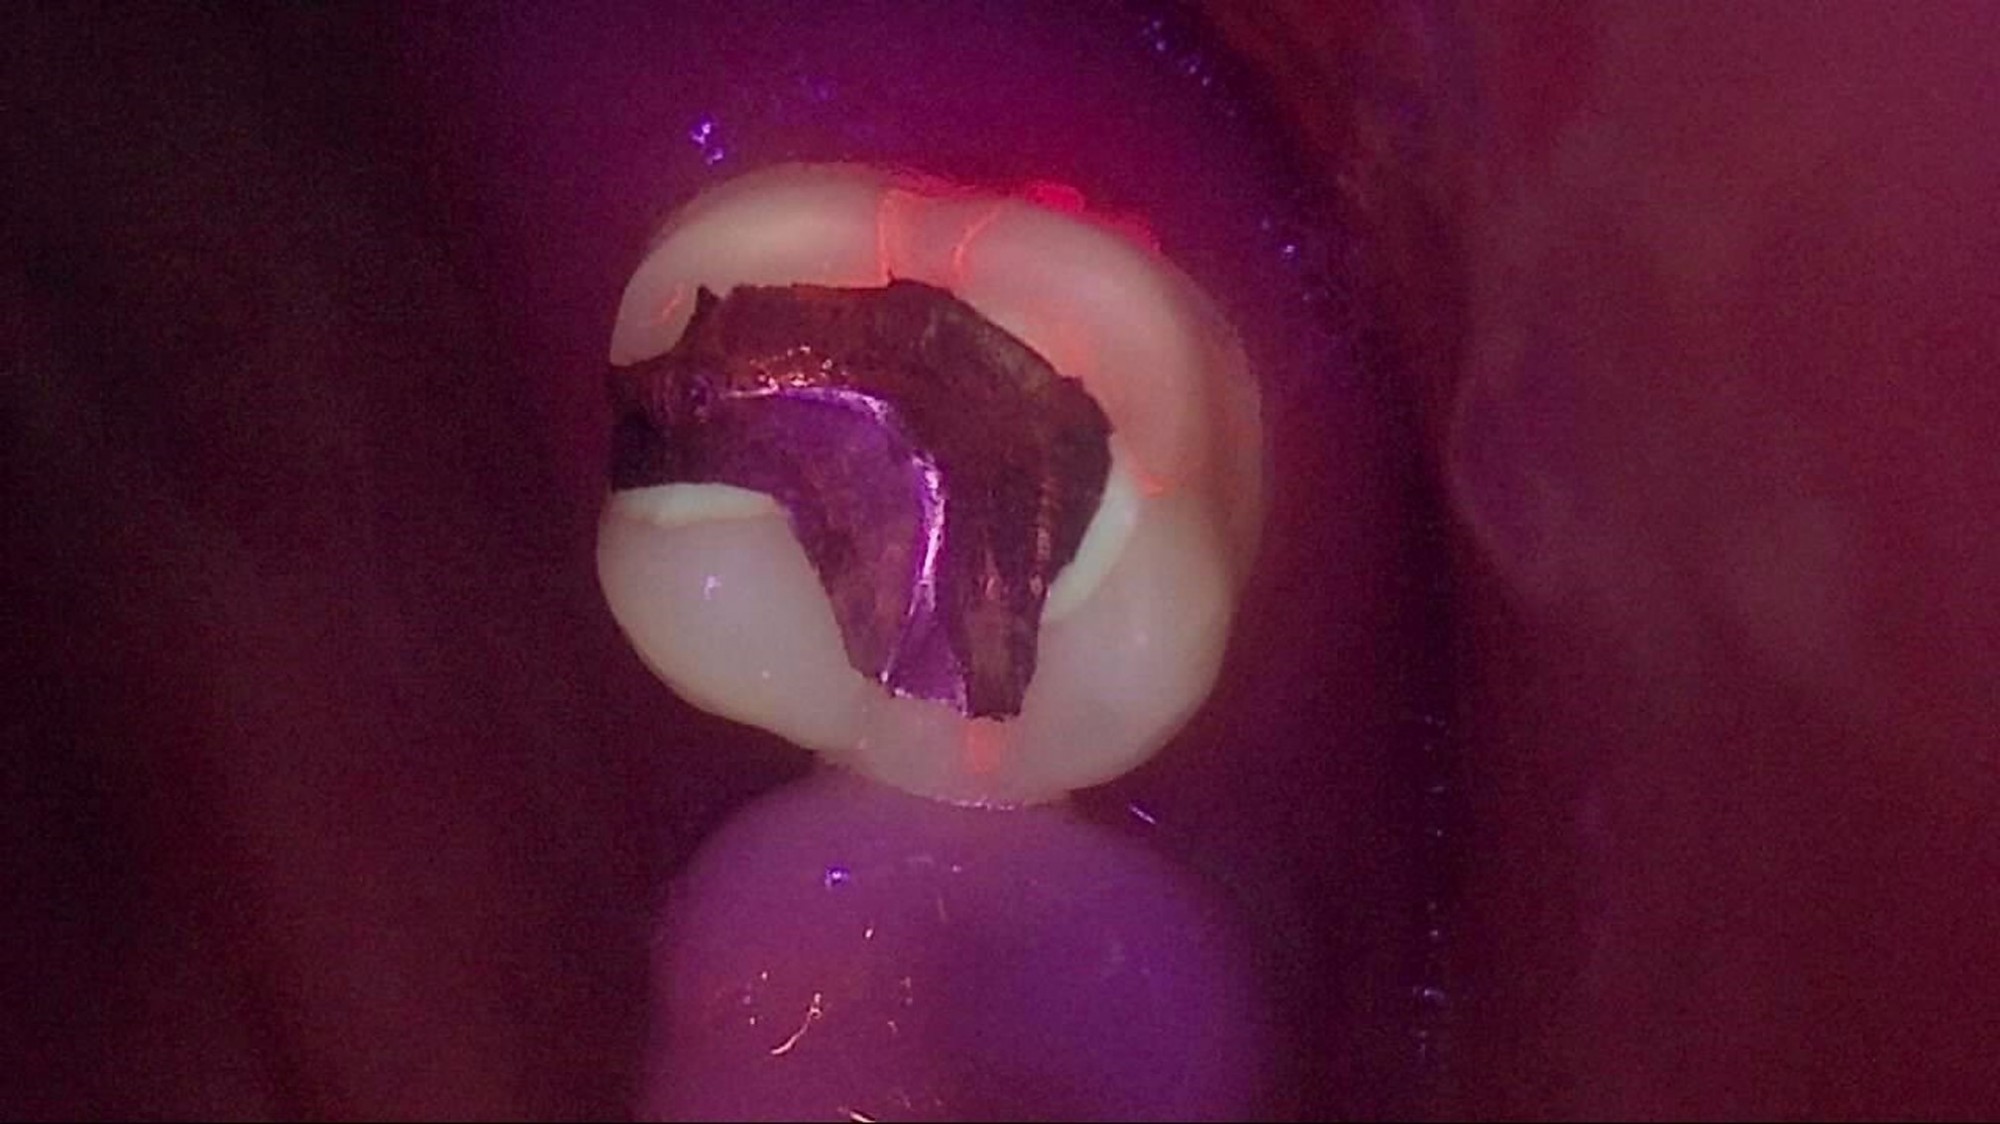

Crack

큐레이캠프로, 큐레이펜씨